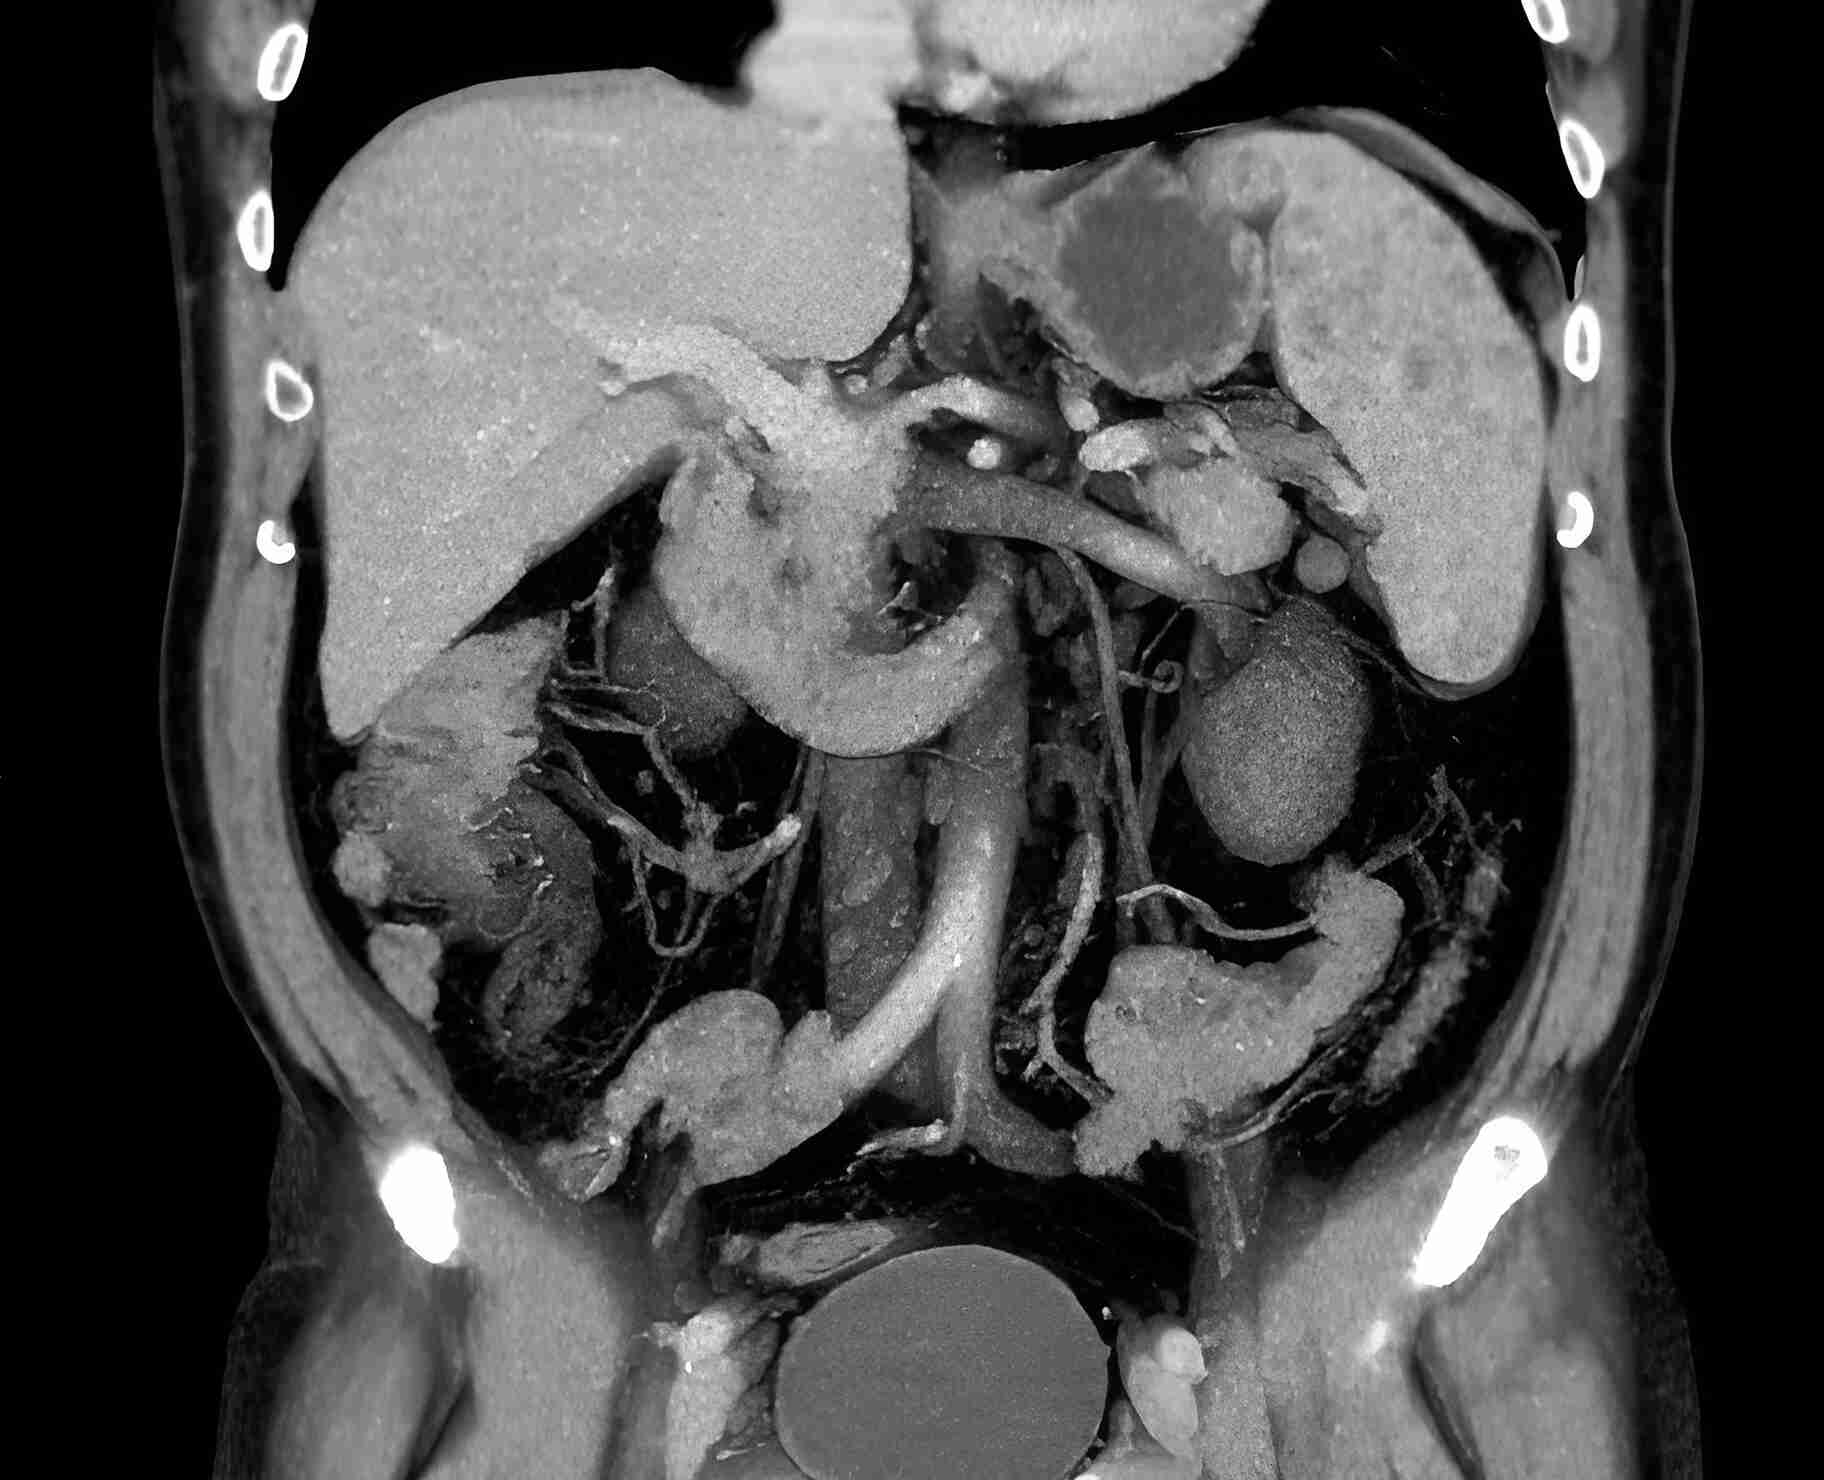

Фотографии и снимки КТ легких без контрастных веществ

Раздел: Визуальный дайджест